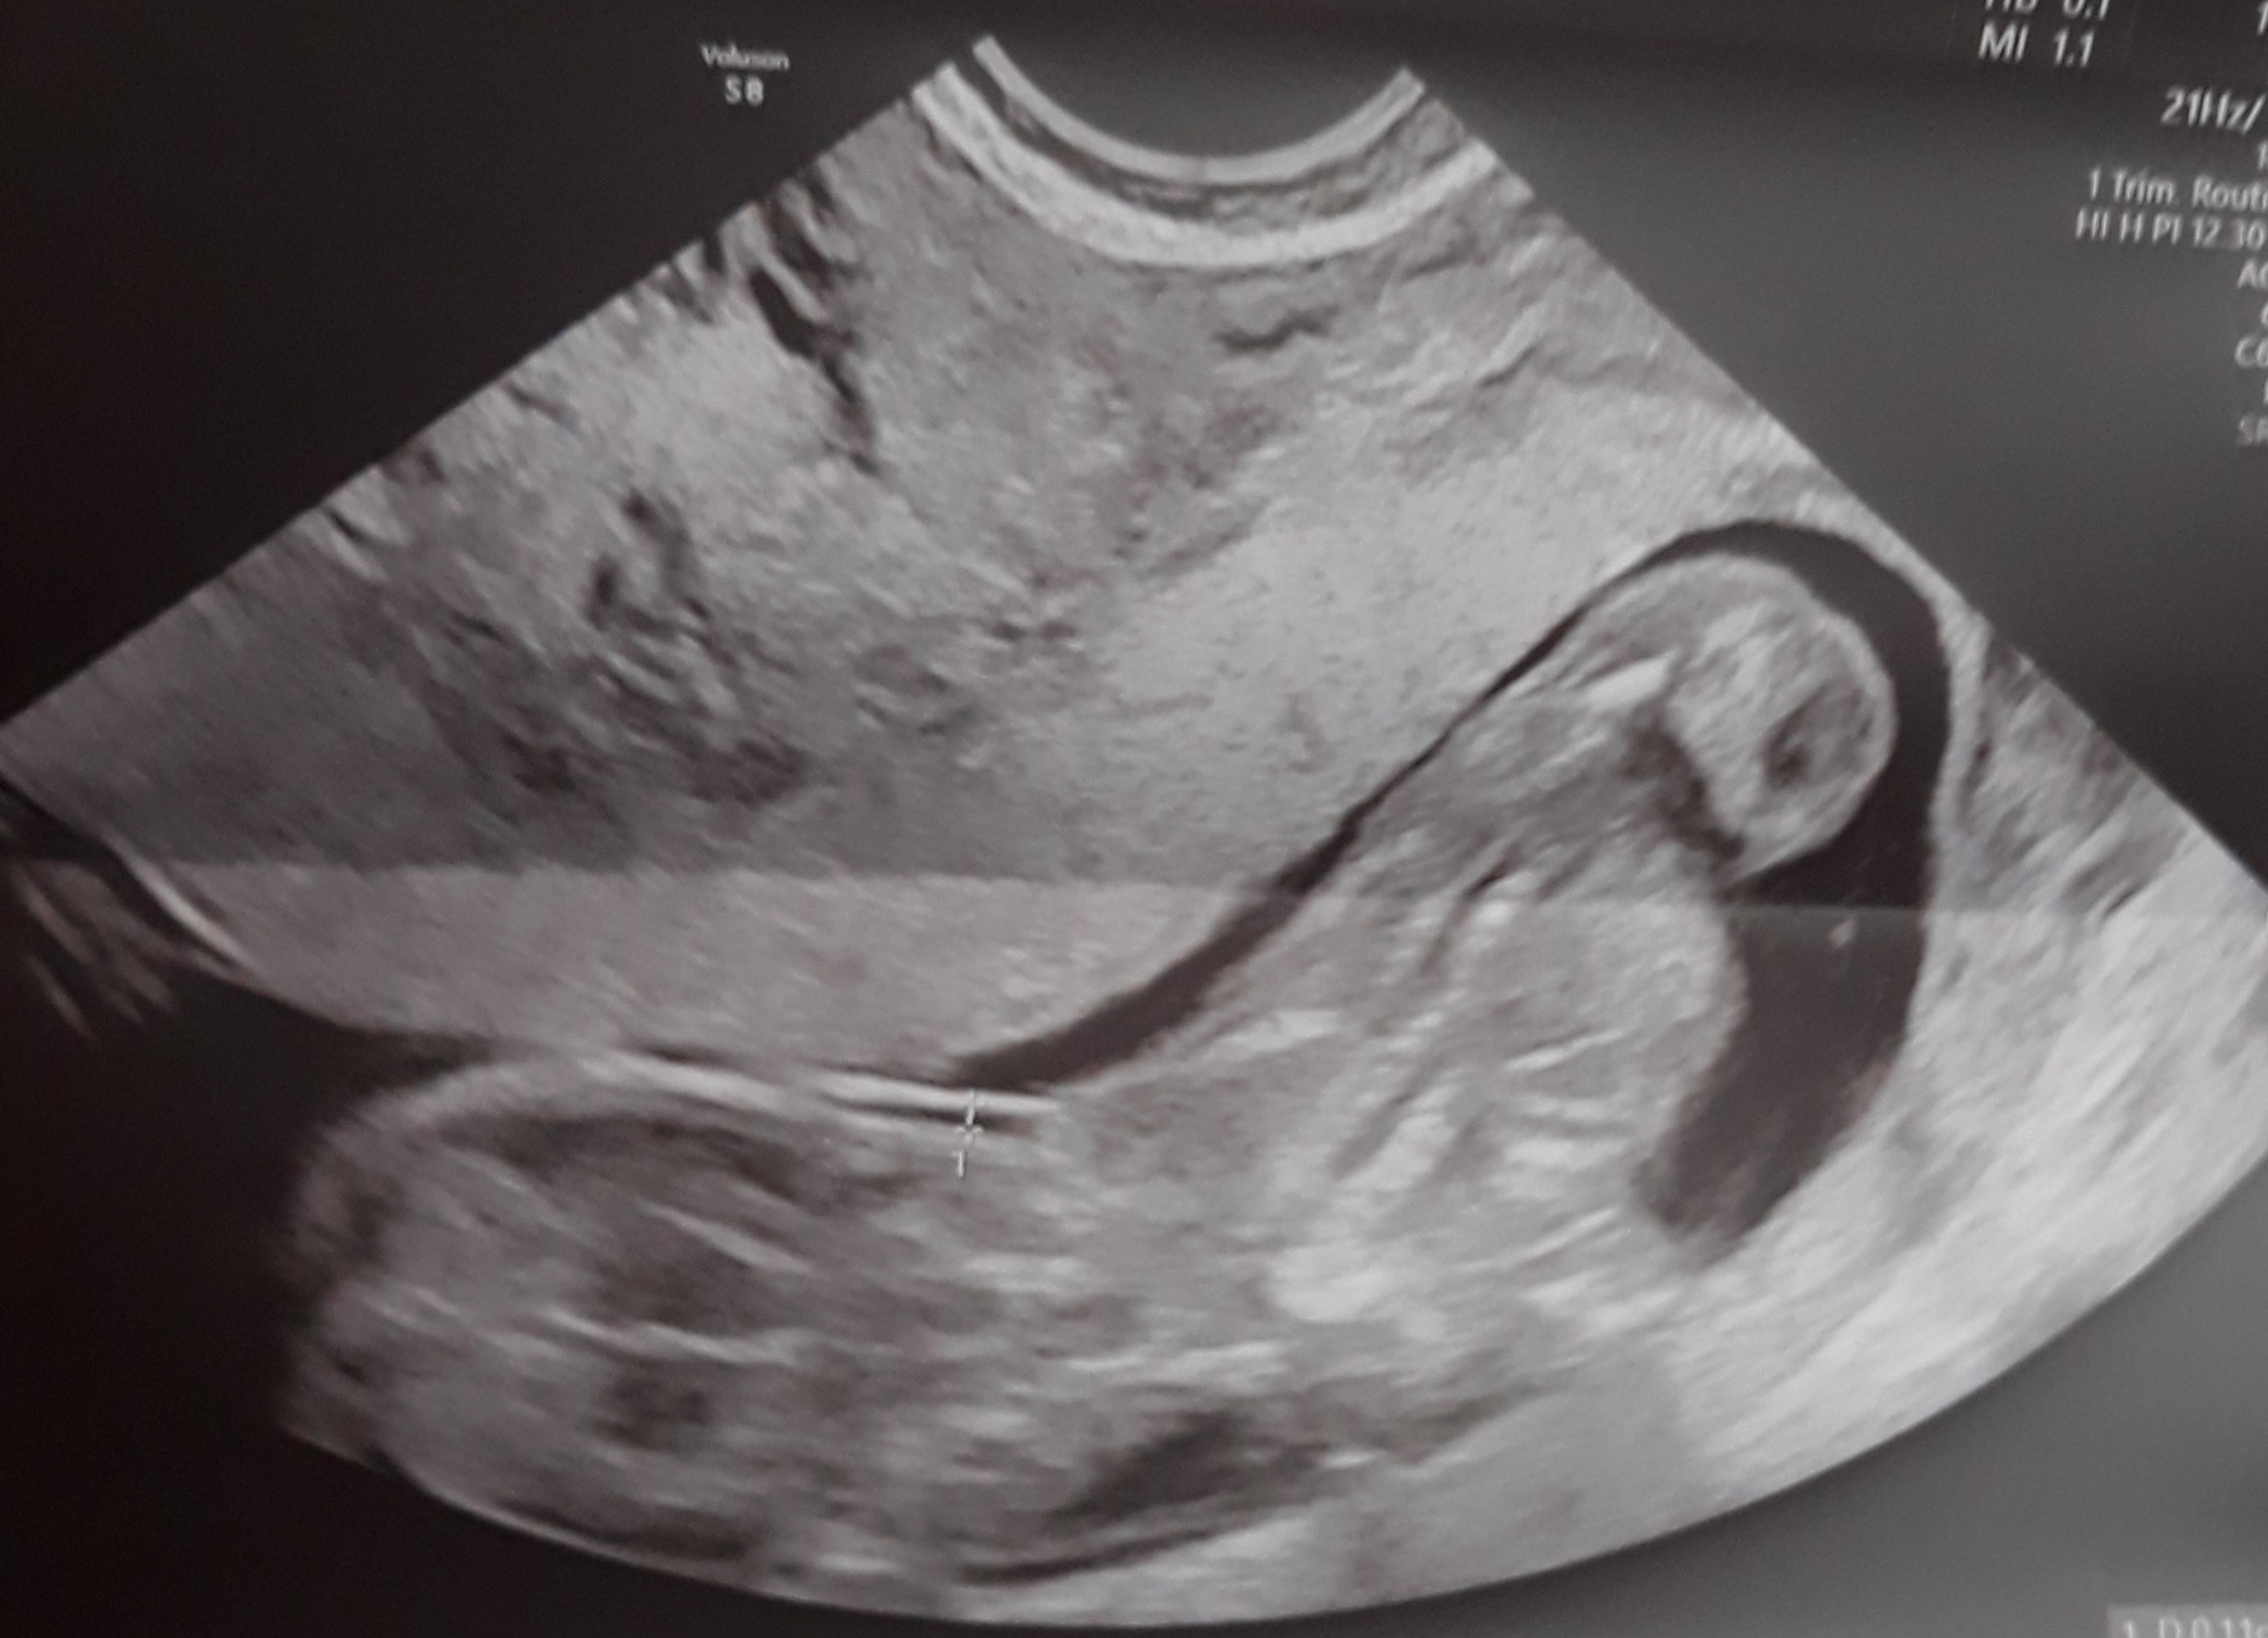

Tylko takie zdjęcie masz ? Wygląda trochę jakby była próba łapania przezierności, ale dziwnie nie bokiem tylko tyłem, to drugie chyba jest z pomiarem crl i wygląda na pierwszy rzut oka lepiej, ale też bez szału. Dzidzuś się mocno ruszał? Słabe to zdjęcie, a to ważne usg, masz opis taki porządny ze wszystkimi pomiarami itd.? Jak nie to może powtórz u kogoś z lepszym sprzętem...

Przemyśl w takim razie czy nie zrobić gdzieś jeszcze prenatalnego u specjalisty z certyfikatem... Może to tylko kwestia zdjęć/sprzętu czy coś ale to zdjęcie nie wydaje się być dobre na oko laika- np. moje dziecko na obydwu usg wykonywanych w podobnym czasie wyglądało inaczej. Nie zrozum mnie źle - nie chce straszyć ani żebyś się bez sensu martwiła, ale nie masz żadnej informacji ani opisu, a tak też nie powinno być.